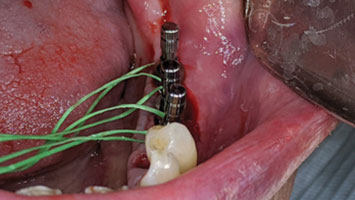

Edentulism in the posterior maxillary region presents a challenging scenario for dental implant rehabilitation due to vertical ridge dimension bone loss and the close proximity to the floor of the maxillary sinus. In addition, alveolar ridge width loss and thinning of mucosa is a common clinical scenario in areas of long term tooth loss. To … Read more